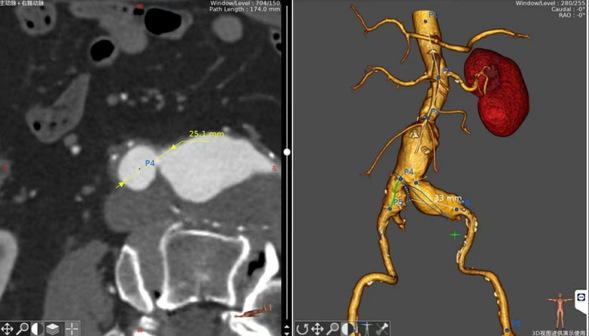

近日,我院血管外科成功“拆除”2025年第一枚“炸弹”。患者唐大爷由于尿潴留来我院泌尿外科就诊,然而这枚埋藏在腹部多年的“不定时炸弹”成了解决排尿不畅的最大阻碍。血管外科李喜春主任团队应邀会诊,向患者及家属详细分析病情,患者于次日转入血管外科完善相关检查。由于病情相对复杂,病变累及双侧髂动脉,经过对动脉CTA各部位精确测量制定手术方案,心内科、胸心外科、呼吸与危重症医学科和麻醉科等各位专家进行多学科会诊评估手术风险,3日后通过杂交手术的形式历时两小时完成手术,患者于术后第二日返回病房,各项生命体征平稳。

术中影像